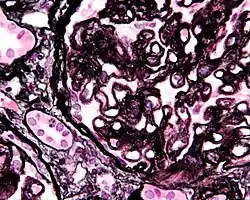

-

Renal corpuscle (glomerulus) showing glomular basement membrane.